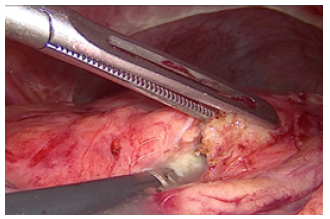

In ten cases we performed laparoscopic cholecystectomy with debridement of pancreatic necrosis. For 18 patients we explored the CBD by choledoscope and extraction of stones was done. The operation was finished with placement of T- tube drainage by laparoscopic approach. In 7 cases was accomplished percutaneous drainage of WOPN under US-control. For eight patients was applied a two-stage procedure. The first step was a placement of percutaneous biliary drainage under US-control and C-arm control. The second step was laparoscopic necrosectomy. A temporary loop ileostomy was performed in 5 cases because of bowel paralysis around the pancreas, paralytic ileus, abdominal distention and worsening of the patients’ condition. Debridement by laparoscopic access was accomplished by transgastric approach or gastrocolic access to enter the lesser sac. Applying a gentle blunt removal of necrotic tissue around pancreas, we take care of blood vessels around the pancreas, and we usually use a bipolar coagulation in case of bleeding from vital pancreatic tissues. We always take a sample from infected tissues for culture and subsequent precise antibiotic treatment (Figure 3).

Debridement of necrotic material was performed by forceps and with a laparoscopic irrigation/suction device with evacuation of infected debris (Figures 4-6).